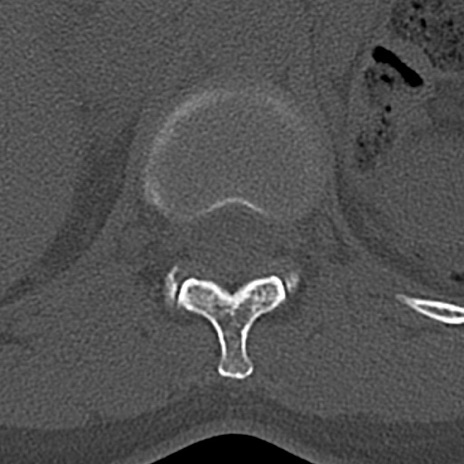

腰椎CT

横断像と矢状断像